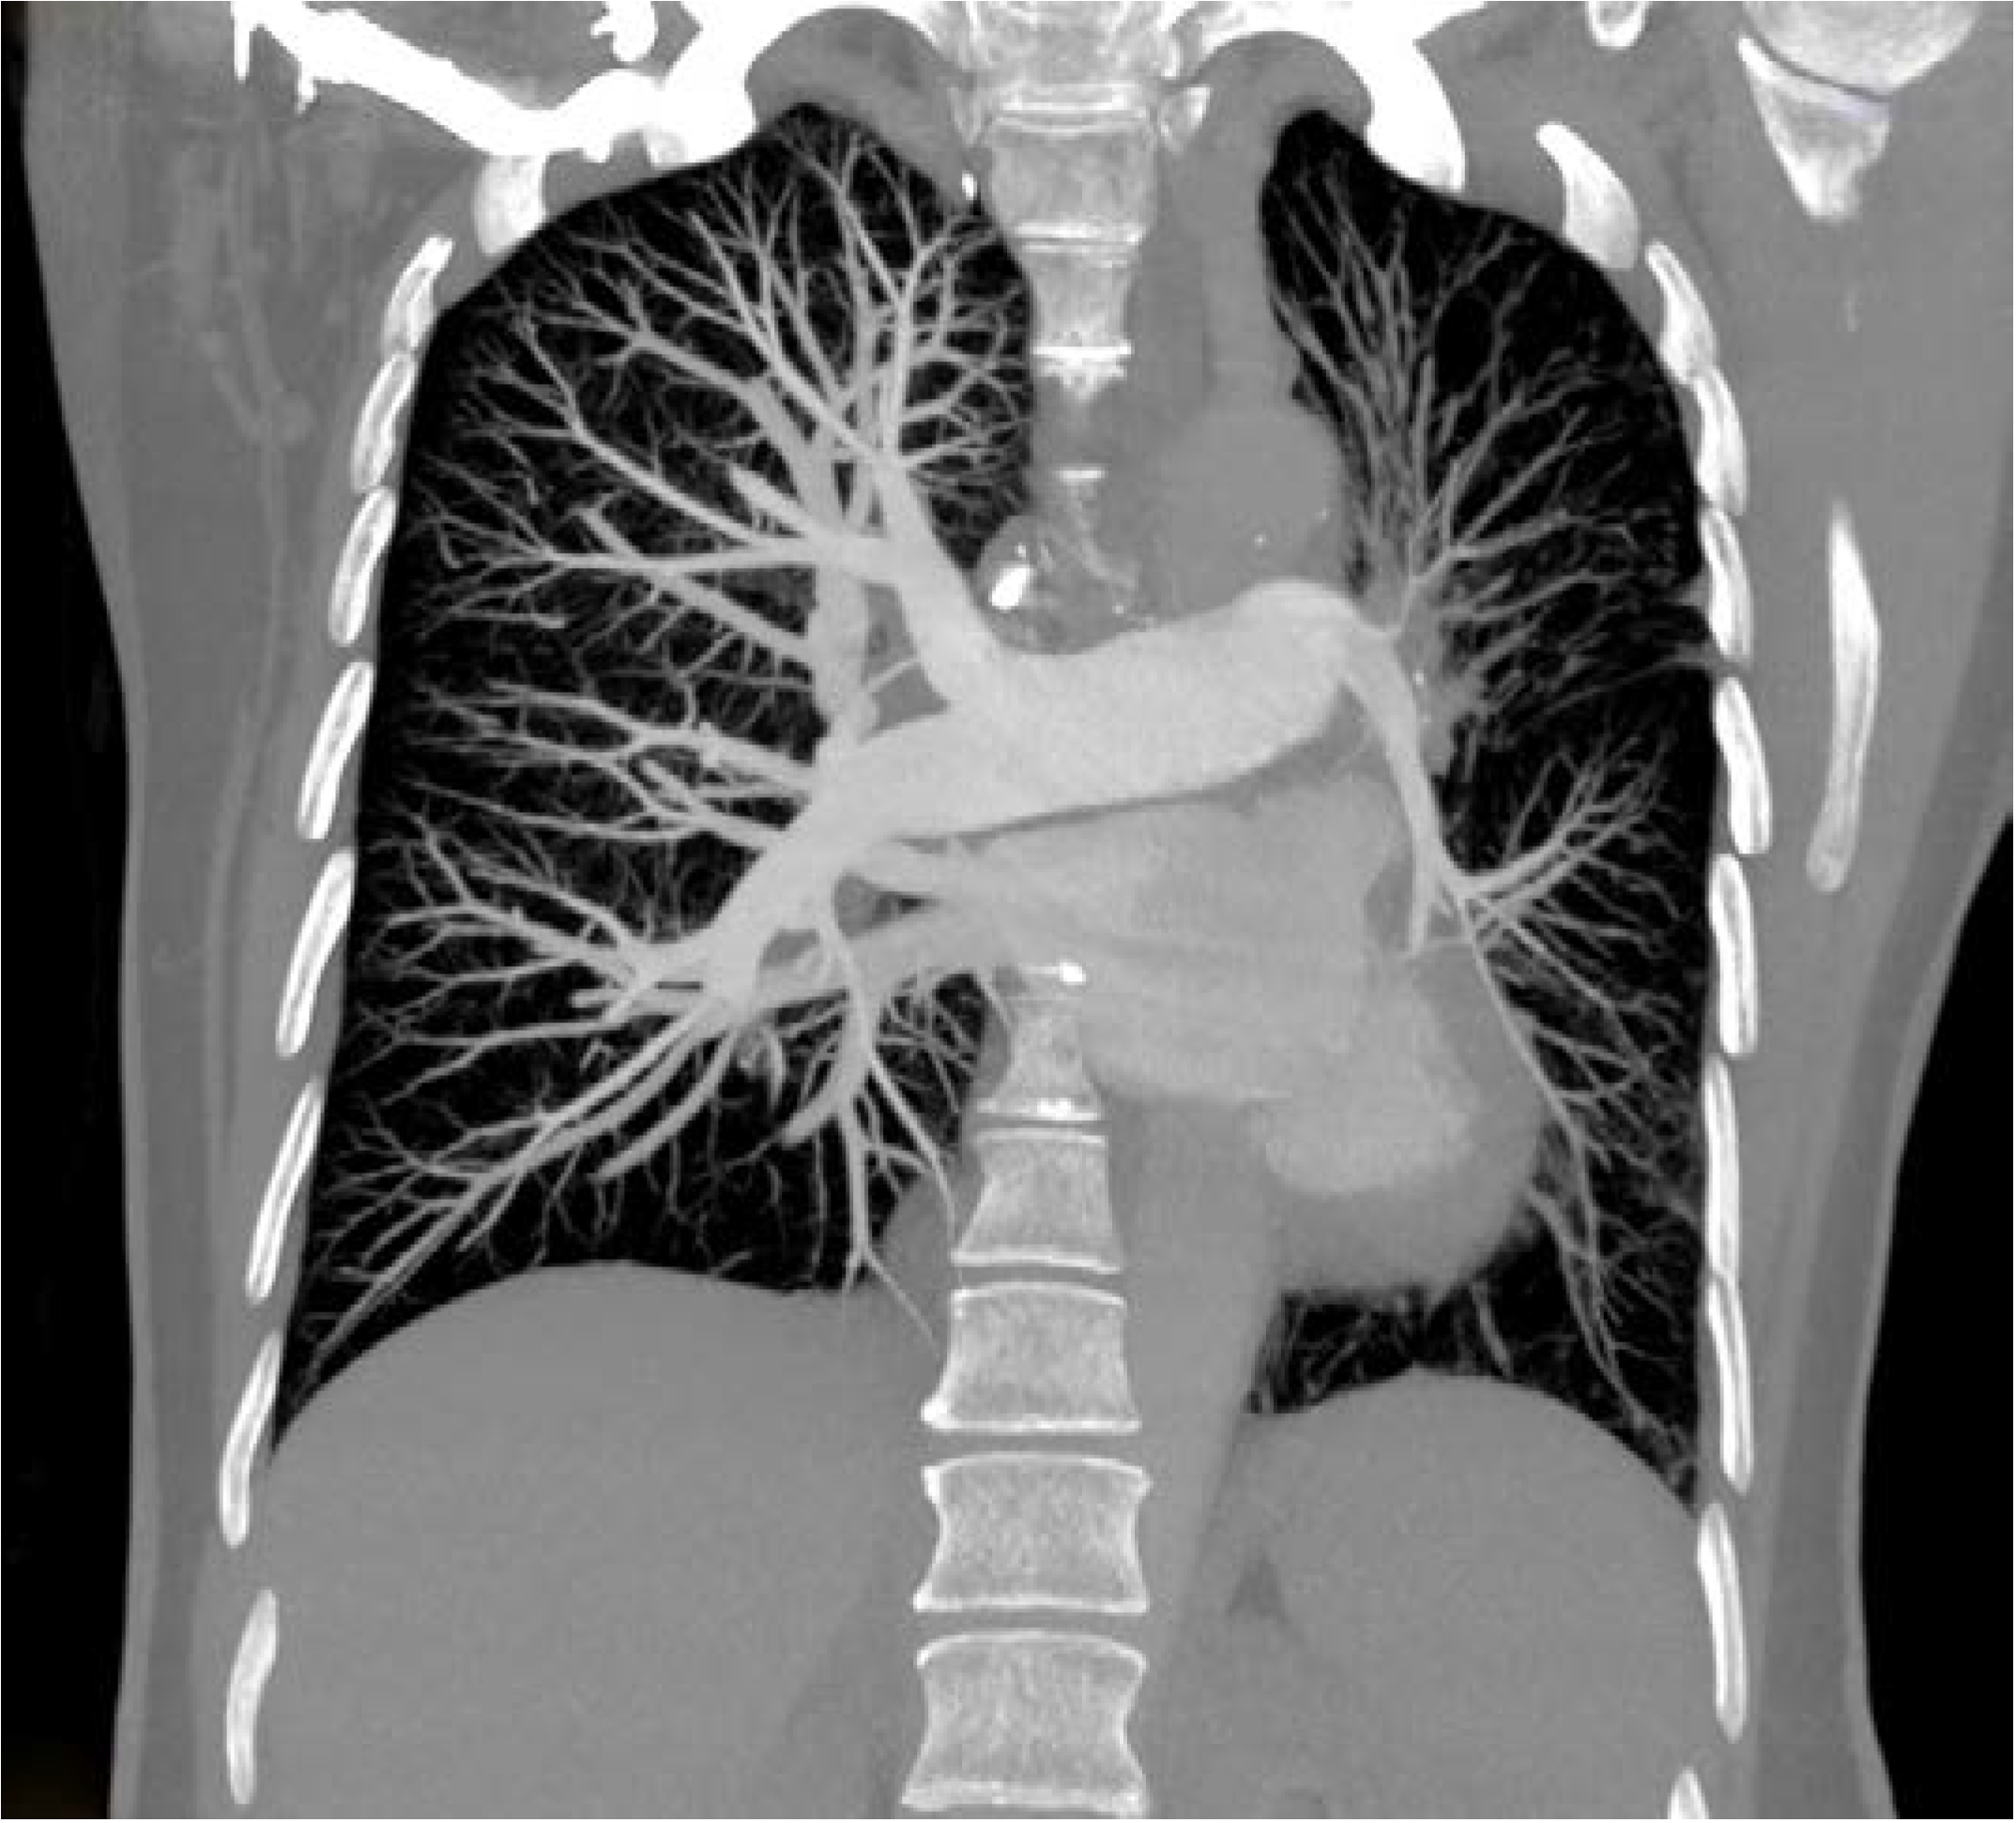

Thorax computed tomography (CT) revealed asymmetry with significantly smaller left lung. The left pulmonary artery immediately after separation was of extremely narrower lumen and so were lobar and segmental branches (Figure 2). Collaterals stemmed from mammary artery and bronchial artery (Figure 3). The results pointed towards UAPA. Subpleurally on the left, apically and basolaterally, scarred changes were noticed.

Thorax CT reveals abnormal pulmonary artery that can be completely absent or finished 1 cm from its beginning or continuing in very narrow lumen, there can be preserved peripheral branches of the pulmonary artery, variable collateral circulation, possibly associated congenital anomalies, parenchymal changes such as mosaic attenuation and bronchiectasis due to recurrent infections [6,10].